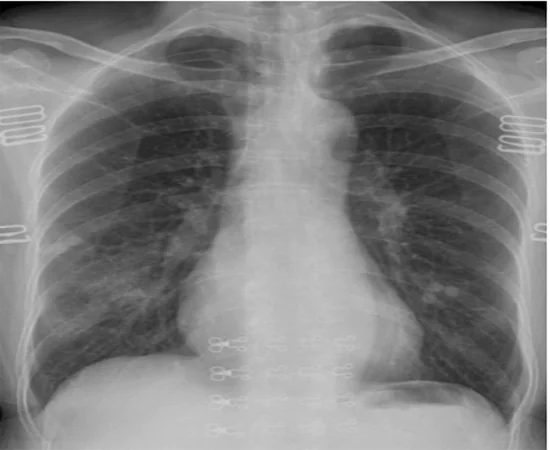

There are many more applications of AI in Covid era. AI may be used to supplement mobile health applications where smart devices such as watches, phones, cameras, and a variety of wearable devices can be used for diagnosis, contact tracking, and efficient monitoring. In telemedicine, applications like AI4COVID-19, which rely on audio recording samples of 2 s cough, can be employed. Also, COVID-19 instances were detected and quantified using AI from chest x-ray and CT scan pictures. COVID-19 detection neural network (COVNet) is a deep learning model that uses visual 2D and 3D characteristics derived from volumetric chest CT scans to distinguish between COVID-19 and community-acquired pneumonia.